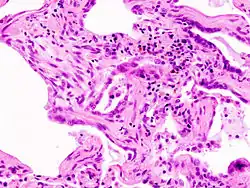

![]() | |

| End-stage pulmonary fibrosis of unknown origin, taken from an autopsy | |